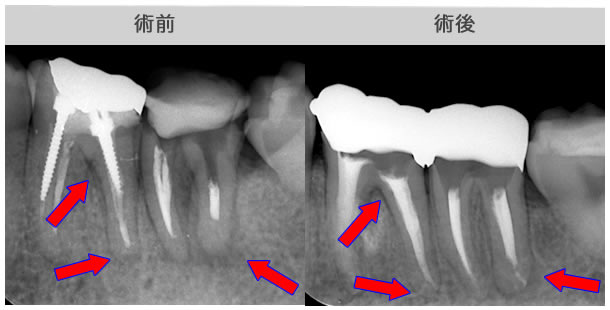

原因は赤の矢印が指す、根の周りの病巣でした。

治療後は青い矢印が指す場所には、黒い病巣が消失しています。

| 治療説明 | 自覚症状で歯が浮いた感じがしていました。上顎大臼歯・頬側根の根尖部にX線透過像の病巣があります。根充剤を除去・拡大清掃・根管充填を行いました。根尖から根充剤がはみ出ていますが、根尖部のX線透過像は見られなくなりました。そこ後、自覚症状もなくなりました。 |

|---|---|

| 治療期間 | 6〜24ヶ月 |

| 治療費用 | 150,000〜300,000円 |

| 治療に伴うリスク | 根管内からの治療で根尖病巣が治らない場合は、外科的に根尖病巣を除去する必要があります。 再根管治療を繰り返す場合、歯根の厚みが薄くなり、歯根破折のリスクが高まります。 |